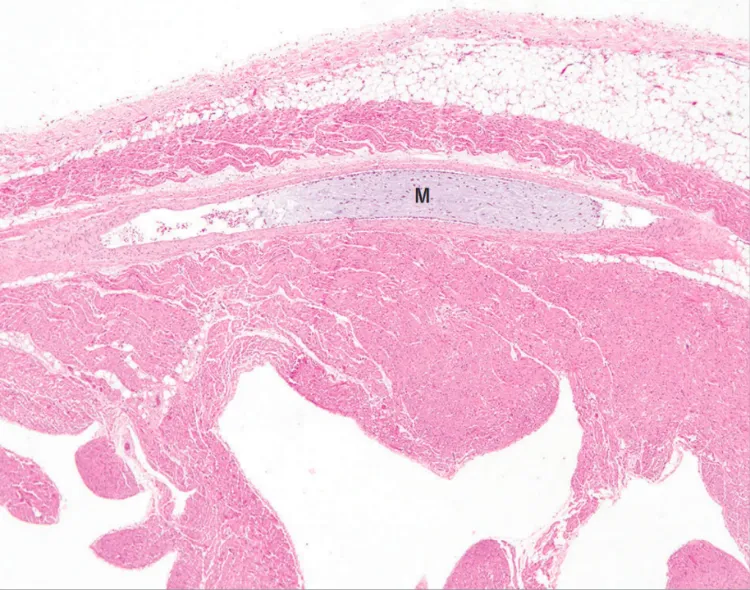

蹦床上的笑声戛然而止时,8岁的双胞胎男孩还没来得及看完这个春天。此前两年,他因为左眼的浅棕色斑块两次活检,病理报告都写着“良性色素沉着”——和父亲、爷爷脸上淡淡的雀斑看起来没什么两样。没人把这个孩子的眼部色斑、胸壁小疙瘩、走路踮脚的习惯联系起来,更不会想到,这些零散的小异常,是一种罕见遗传病递出的最后通牒。心脏骤停的抢救室里,医生还在排查心肌炎和外伤,直到二次尸检的解剖刀划开左心室,才看见那些堵住冠状动脉的、像果冻一样的粘液瘤——这是Carney综合征最致命的手笔。

但真实的发病机制比这个类比更精确:PRKAR1A的突变会让细胞里的cAMP信号通路彻底紊乱,就像把家里的总闸调到最大,所有电器都开始过载运转。心脏粘液瘤是最凶险的“地雷”,它的表面容易脱落血栓,一旦堵在冠状动脉,几分钟就能引发猝死;而那些出现在唇周、结膜、眼睑的色素斑,其实是最早亮起的警示灯——70%的患者在心脏症状出现前,就已经长出了这些斑点。

更关键的是,我们对“良性”的定义太绝对了。病理报告里的“无细胞异型性”不代表身体没有问题,它只说明这块皮肤本身不是恶性肿瘤。Carney综合征的色素斑是“信号弹”,不是“炸弹”本身——可惜的是,没人读懂这个信号。直到尸检报告里写着“左心室多发纤维瘢痕”“冠状动脉栓塞性粘液瘤”,所有人才恍然大悟:那些被忽略的小症状,早已经把这个孩子的身体变成了一个即将爆炸的火药桶。